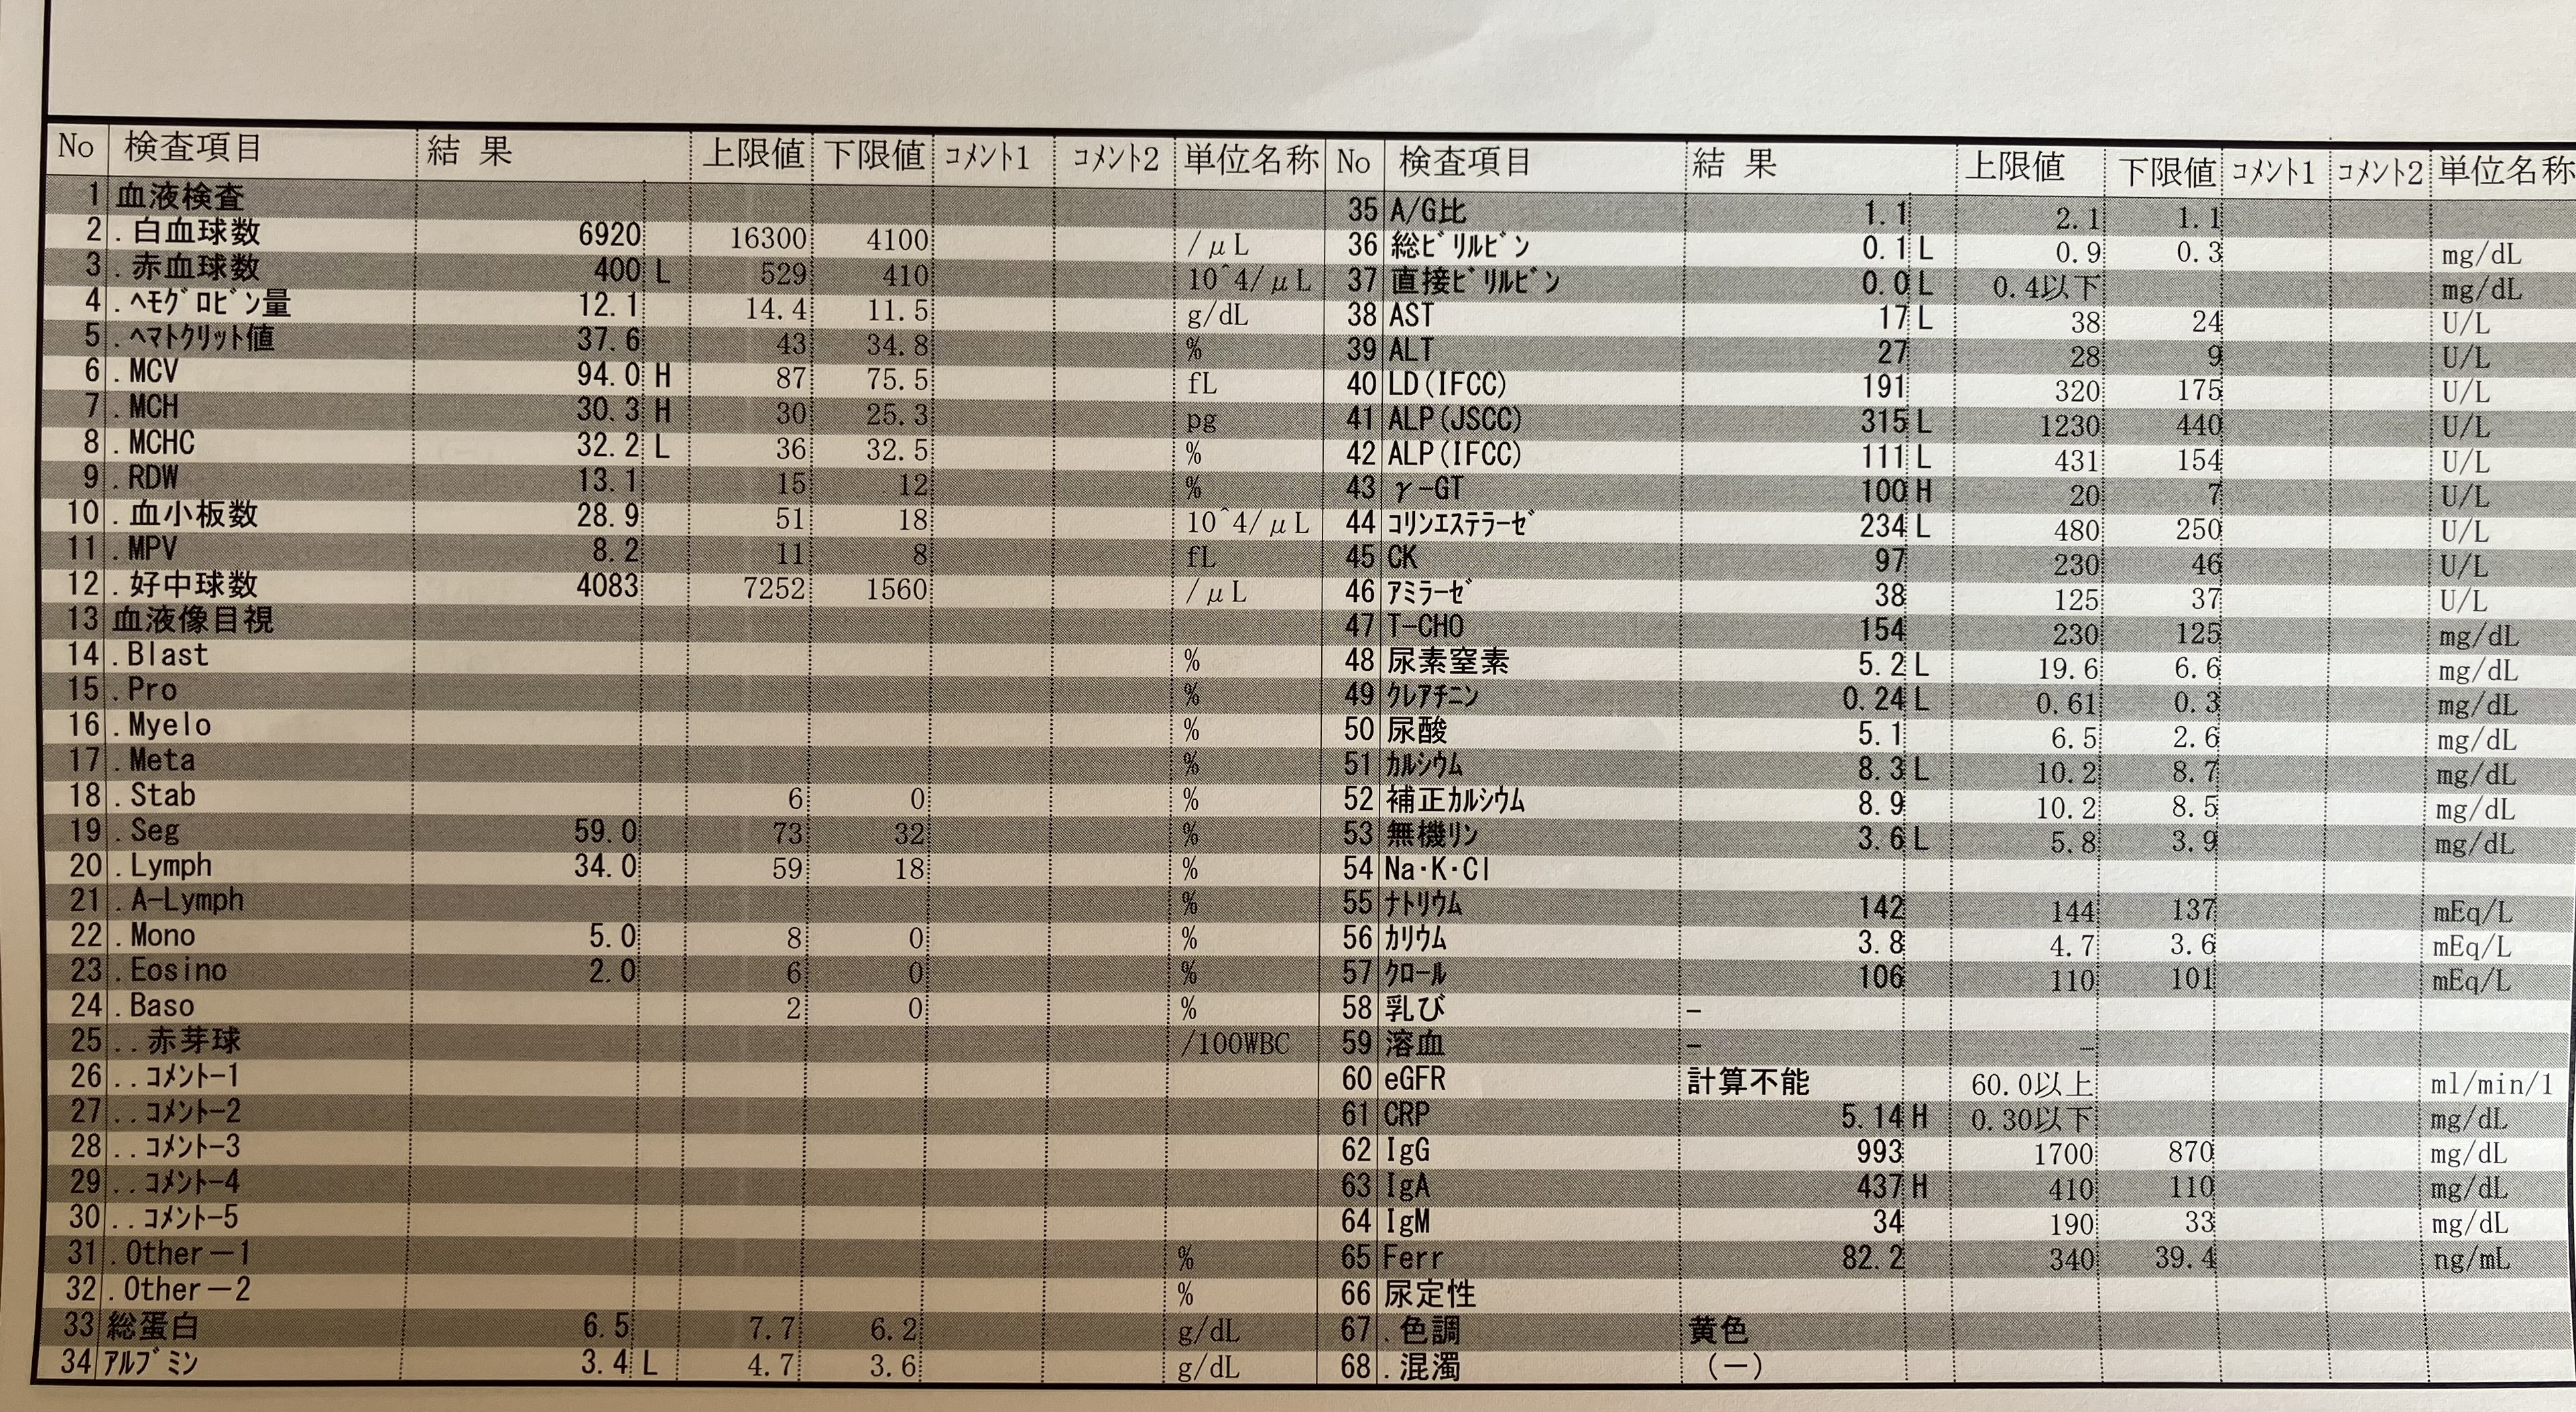

昨日は9時に採血・検尿、レントゲンも撮って、

結果は…

先生「採血とレントゲンを撮ったけど、

まだ左肺が白っぽいのと、炎症値も5と高い。

このまま帰すのは心配だから注射の抗生物質を

しっかり7日間やってから、また結果を見ましょう。

退院は延期です。」

ということで…

退院はもう少し先になりました😢

改善傾向にはあるので、

しっかり治してから帰ろう💪